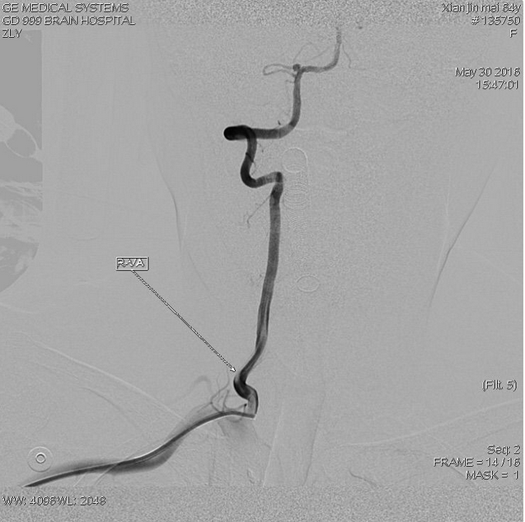

栓塞后动脉瘤不显影,瘤颈口与动脉开口处稍残留,小脑后下动脉显影通畅

Livs(212517)支架辅助栓塞后交通动脉瘤,动脉瘤不显影

栓塞后不减影,弹簧圈形态符合动脉瘤形态

支架完全打开,与血管贴壁良好,覆盖瘤颈口满意